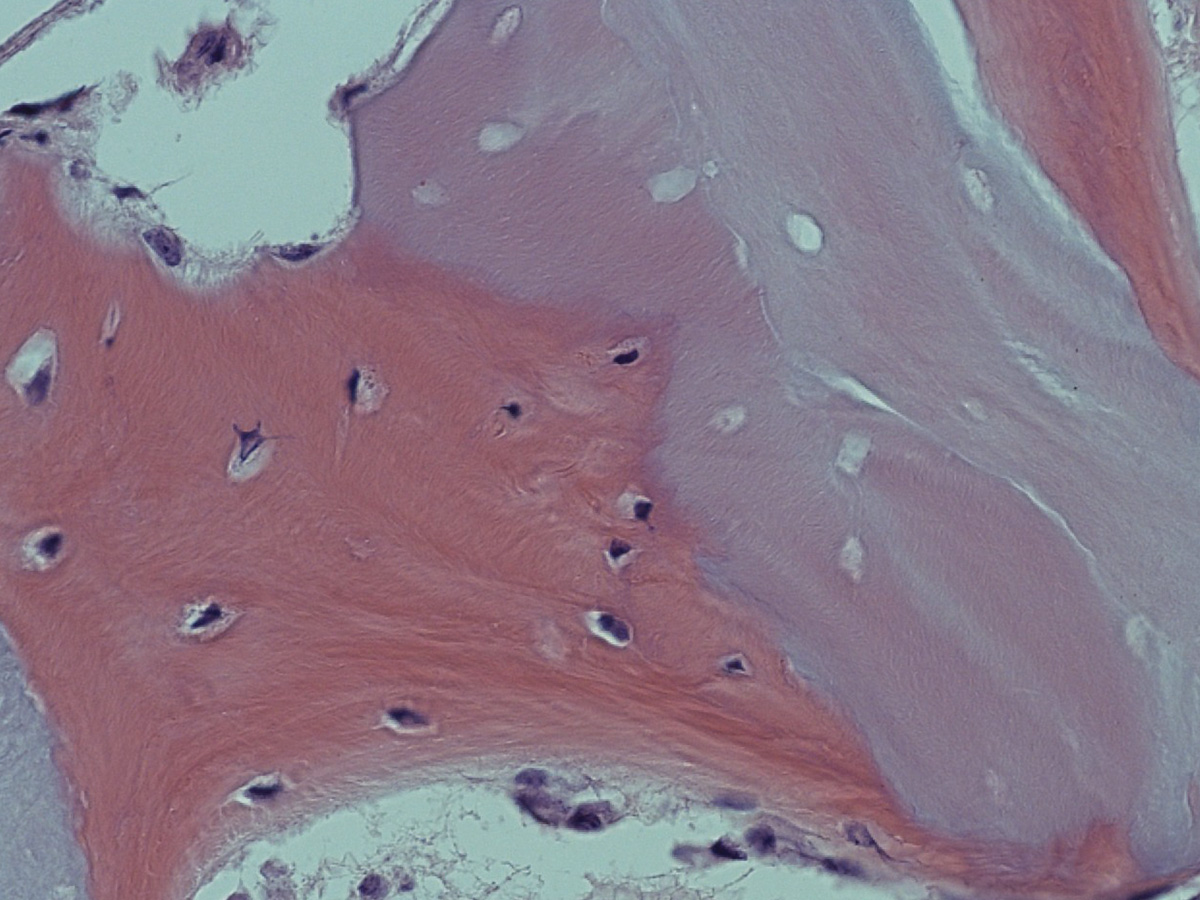

Biopsate aus der Maxilla, Entnahme nach vier Monaten.

Abbildung 11

Histologie bei stärkerer Vergrößerung: In den Resorptionslakunen sind Osteozyten erkennbar.